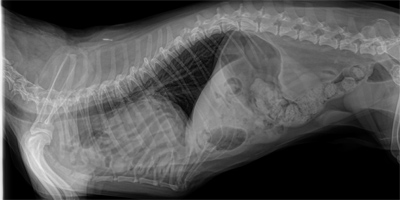

Why is this Pekingese vomiting?

June 1, 2018

This 10 year old male Pekingese was presented for vomiting. Questions: Describe the radiograph. What is your diagnosis? Explain the surgical steps. What is a critical precaution preop?